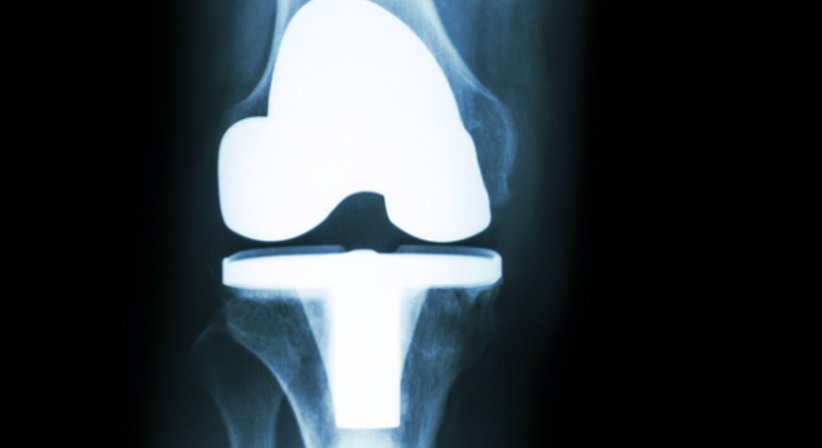

Für Patienten mit sehr stark fortgeschrittener Arthrose im Knie (Gonarthrose), bei welchen konservative Behandlungen und minimal-invasive Eingriffe zur Behandlung der Arthrose und der damit verbundenen Schmerzen nicht mehr wirksam sind, stellt die Implantation einer Knieprothese die einzige effektive Maßnahme für langfristige Beschwerdefreiheit dar.

Bei der implantierten Knieprothese handelt es sich um ein künstliches Kniegelenk, welches das Kniegelenk teilweise (z.B. Ersatz des trochleären Gleitlagers, "Wave") oder zur Gänze ersetzt (Knietotalendoprothese).

Knieprothesen zählen zu den am häufigsten implantierten Endoprothesen. Für die Implantation stehen unterschiedliche Knieprothesen zur Wahl, die sich in ihren Größen, Varianten und Formen unterscheiden. In der Ordination greifen wir auf hochmoderne und dem neuesten Stand der Wissenschaft entsprechende Endoprothesen zurück, die sich durch eine hohe Sicherheit und Patientenzufriedenheit auszeichnen.